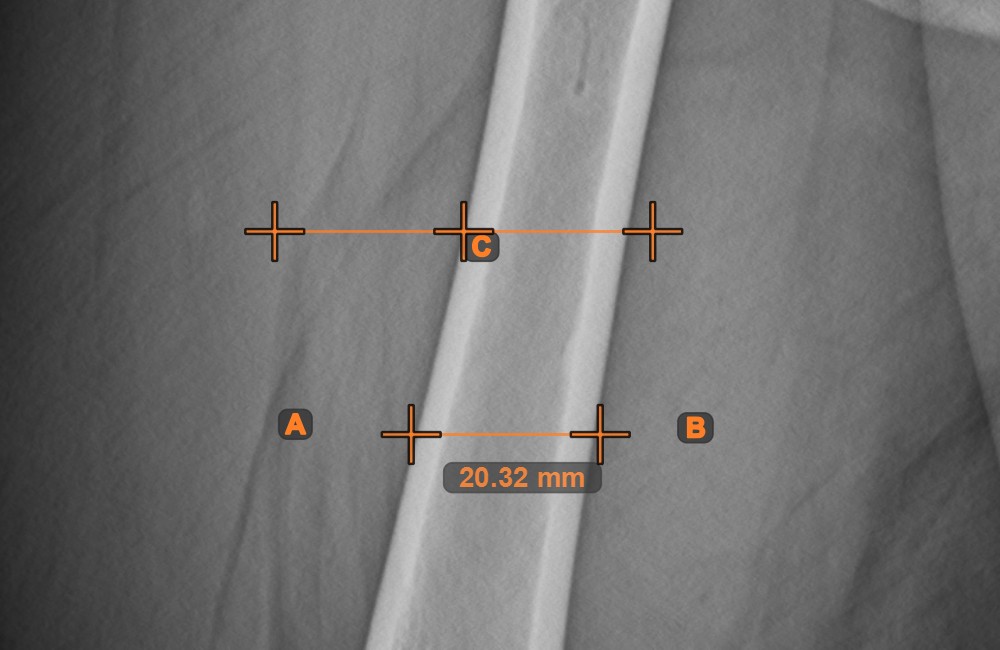

Line Measurement¶

Select the Line Measurement tool and assign it to one of the available mouse buttons. Place the start and end points on the scene or select them from already existing points on the image. The distance between the two points will be automatically

calculated by using the default calibration data, or the recalibrated data by the length calibration measurement.

Modify the start and end point by using the Select/Move Item tool. The distance between the two points will be automatically recalculated.

Center Point of Line¶

Identify and mark the center point of a new or existing line measurement on the scene by using the Center Point of Line tool.

Select the tool from the left toolbar and assign it to one of the available mouse buttons. Place the start and end points on the scene, select them from already existing points on the image, or select an already drawn line from the scene. The center point of the line will be automatically calculated and placed on the scene. The center point of each line will always be marked with the letter C.